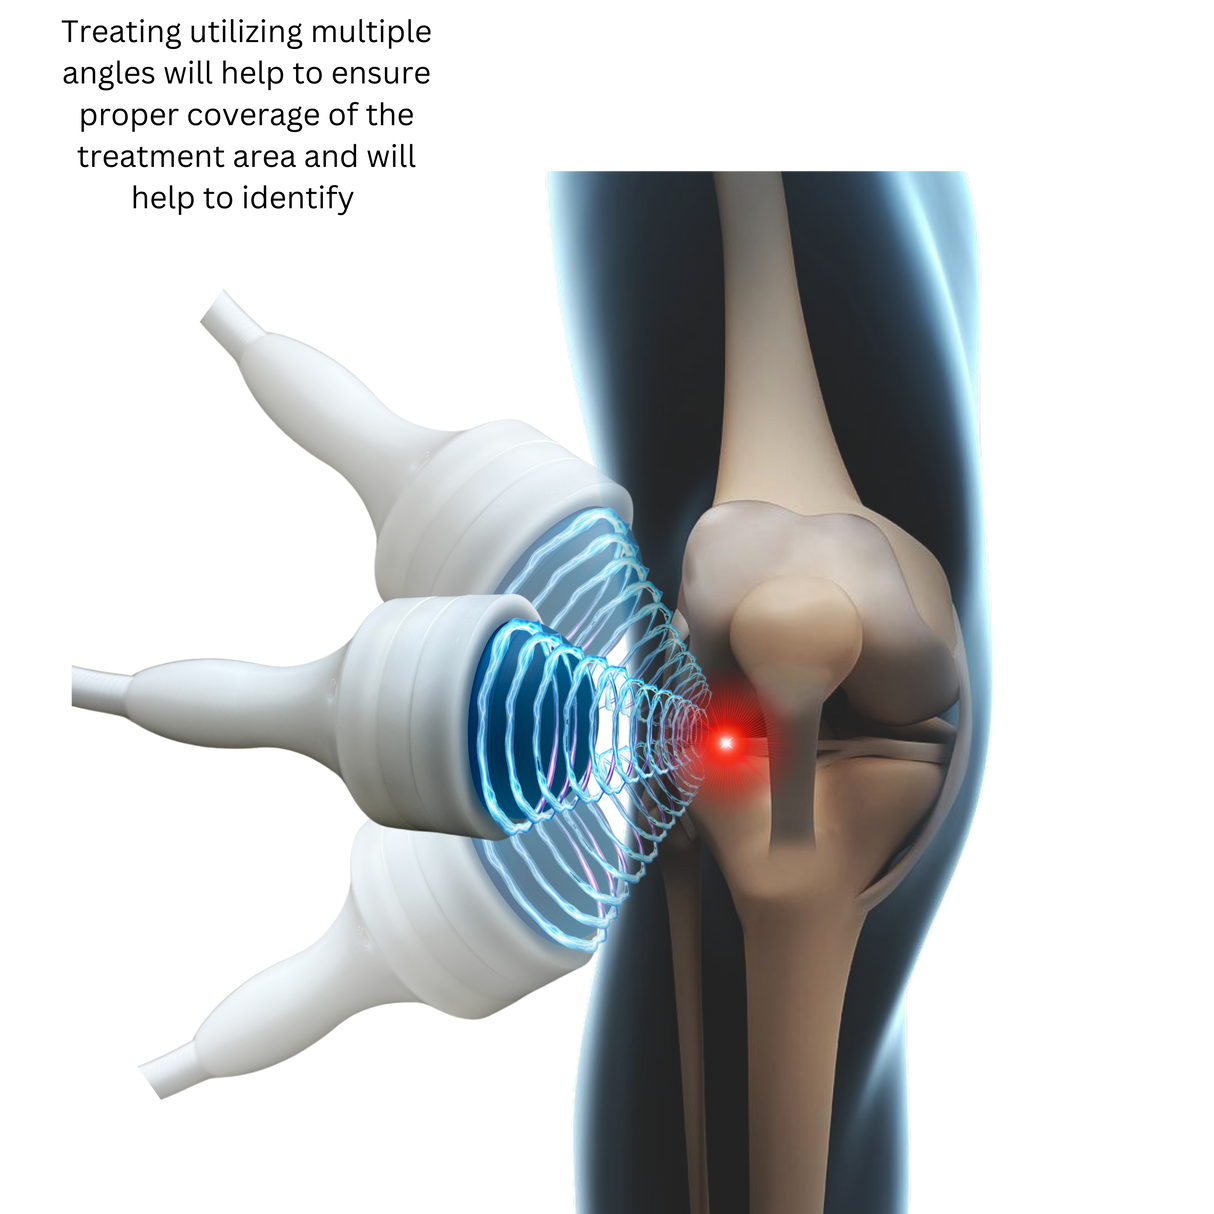

Electromagnetic Precision:

Eliminates spark-gap inefficiencies, delivering consistent pressure for deeper penetration. -